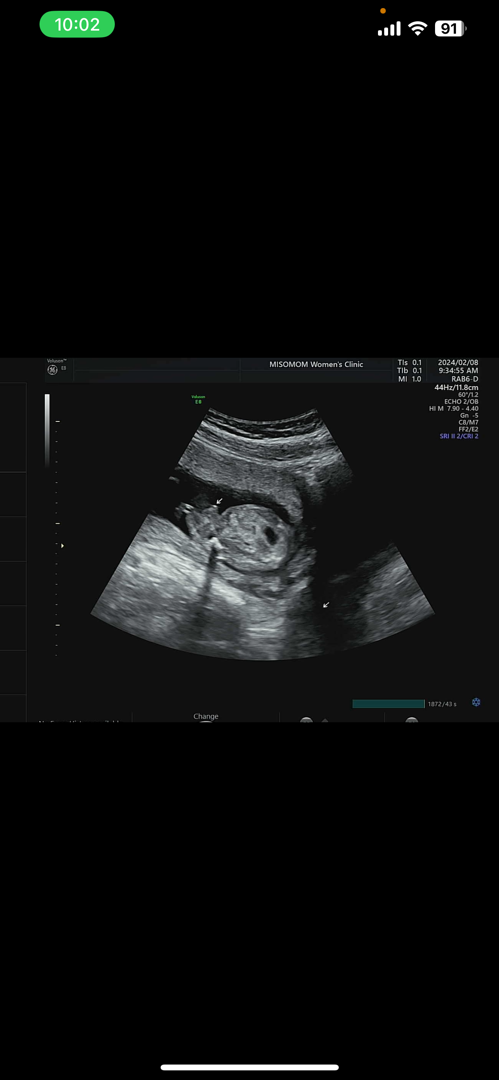

15주.... 선생님도 긴가민가하시는데 아들같다고하네요 ㅠㅠㅠ 첫찌가 아들이라 딸을 원했긴했는데 또 아들일까요...

넹 튀어나왔네요